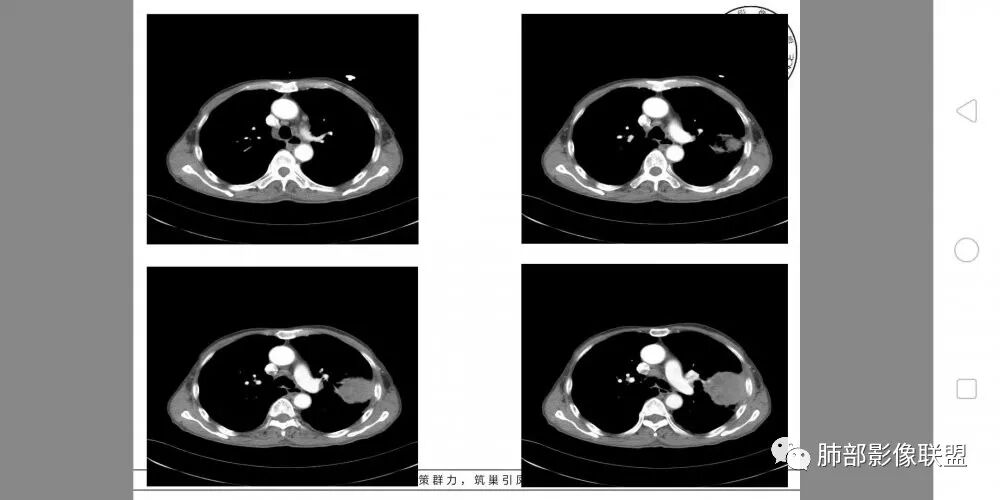

左肺上叶实性肿物,左肺上叶支气管受压变窄,病灶边缘光滑,轻度分叶,病灶轻度强化内部可见多发小灶坏死,坏死边界模糊,病灶突破壁层胸膜侵及左侧部分肋骨及肋间肌,考虑恶性,肉瘤样癌,鉴别诊断低分化腺癌。

定位,肺内,左肺上叶肿块,推移左肺上叶支气管向前移位,无阻塞,边界清楚,光滑,增强有坏死,强化,向外侵及胸壁及肋骨,恶性肯定,病理间叶来源,肉瘤?,肉瘤样癌?大细胞肺癌?

左肺上叶占位,支气管无明显阻塞,上下舌段支气管受压推移为主,分叉角增大,胸壁受侵犯,肋骨骨质破坏,考虑肺内外朝内的病变,肉瘤样癌?

胸部CT所见左肺上叶尖后段胸膜下较大山丘形肿块,边界清楚,宽基底与胸膜相贴,边缘与胸膜呈直角及锐角相交。邻近上叶尖后段支气管受压推挤,叶裂局部膨隆,病灶周围见少许磨玻璃密度影,边界不清。纵膈窗显示,肿块密度均匀,增强扫描呈不均匀轻度强化,邻近肋骨骨质破坏,病变沿肋间隙向外侵犯,局部胸膜增厚。纵膈内见多发小淋巴结,未见胸腔积液征象。综合考虑恶性占位,肉瘤样癌可能性大。腰椎及髋部考虑骨转移。

病灶与叶裂之间夹有上叶下舌段支气管、血管。舌段支气管后移,尖后段支气管前移,病灶将支气管撑开。

叶裂受压后移,提示病灶不来源于叶裂。

支气管推移-----提示外朝内

近端肺动脉受压外移,但是有部分进入病灶内-------提示与肺有千丝万缕的关系。

病灶的整体形态--肺内边界清晰,膨胀性为主

综合考虑恶性肿瘤,外朝内发展,倾向于肺内来源。